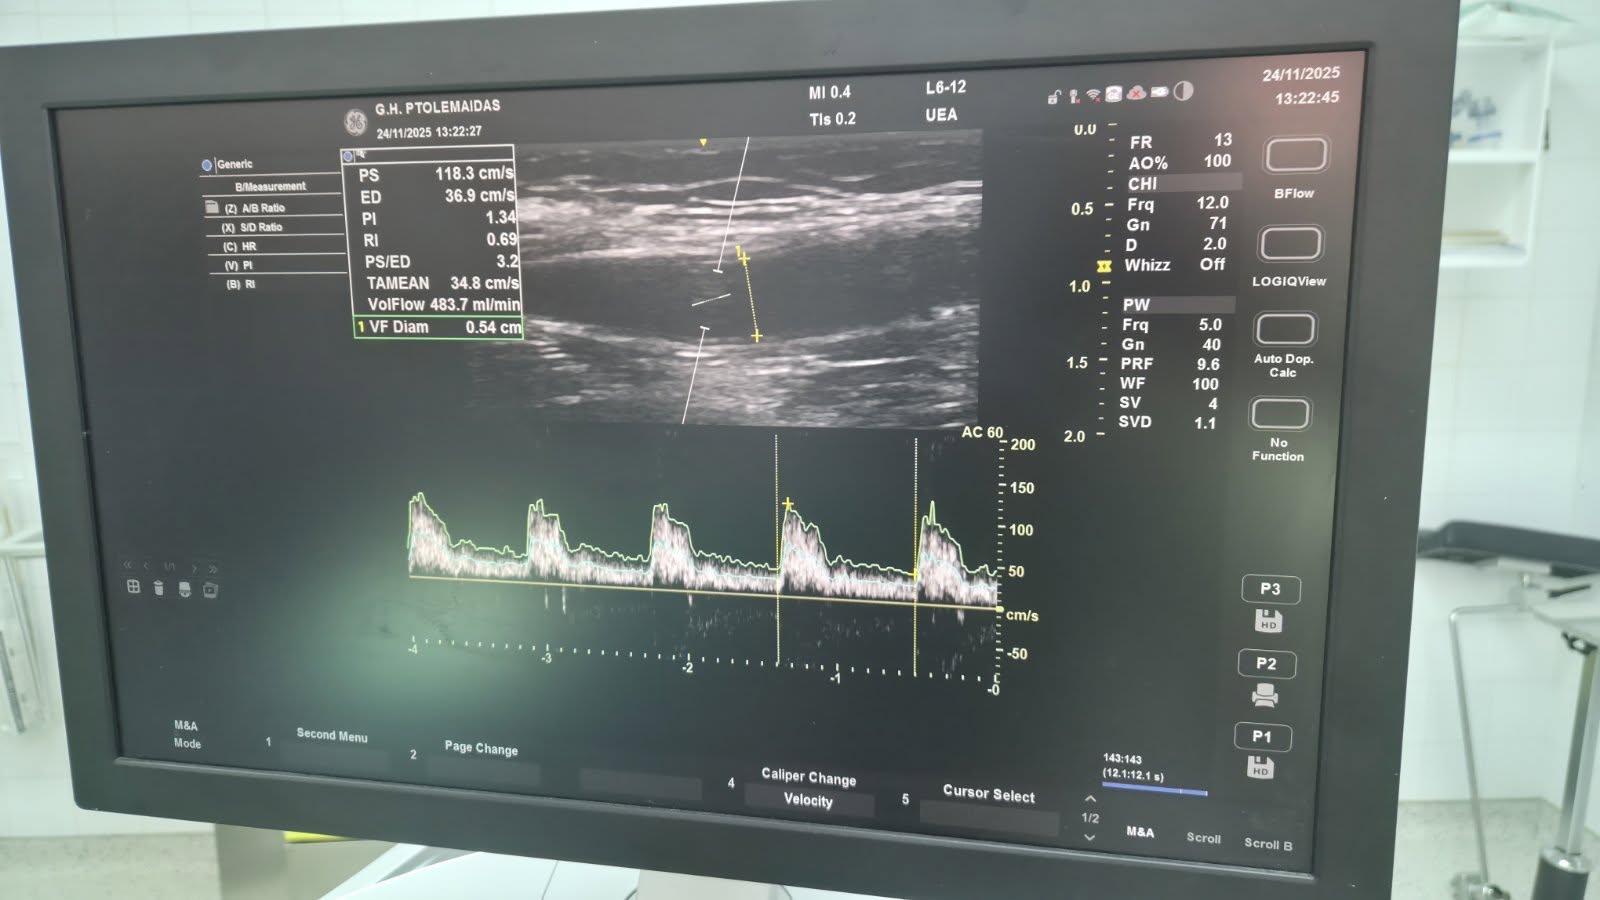

Με ανάρτησή του στο Facebook ο Αγγειοχειρούργος Παναγιώτης Θεοδωρίδης αναφέρεται σε μία πρωτοποριακή επέμβαση που έγινε στο Μποδοσάκειο Νοσοκομείο Πτολεμαΐδας στο πλαίσιο λειτουργίας του Ιατρείου Αγγειακών Προσπελάσεων. Το Μποδοσάκειο είναι το πρώτο Νοσοκομείο στη Βόρεια Ελλάδα που έκανε αυτή την επέμβαση.